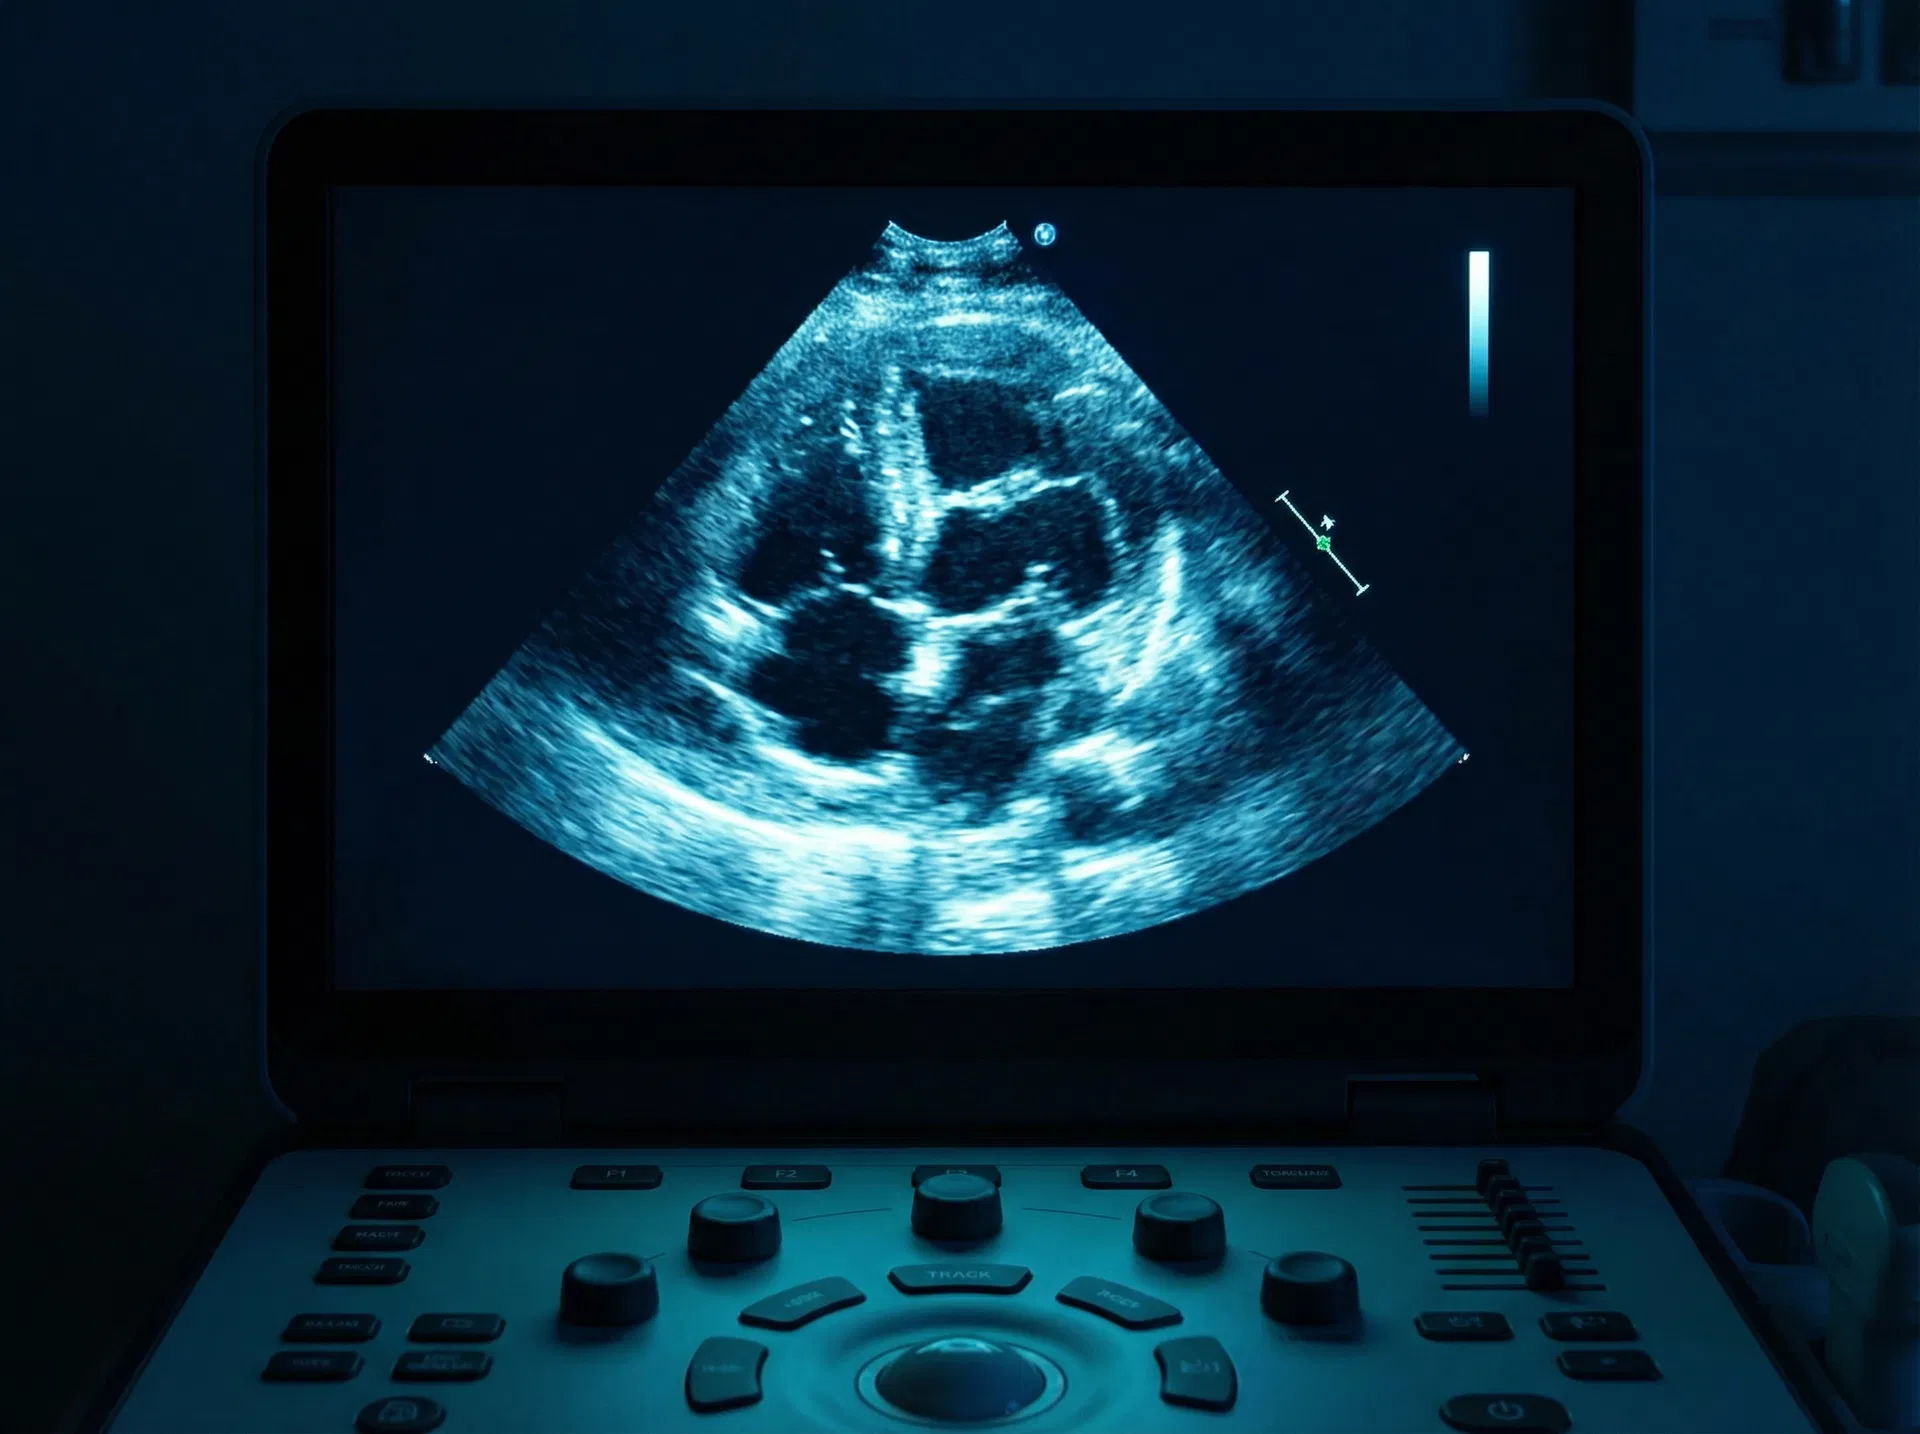

Capacitação em ultrassonografia à beira-leito com protocolos estruturados FAST, RUSH e BLUE. Para médicos e enfermeiros.

Capacitação em ultrassonografia obstétrica à beira-leito para avaliação na sala de parto, pronto-socorro e atenção primária em saúde.

Capacitar Médicos e Enfermeiros na avaliação obstétrica na sala de parto, pronto-socorro ou na atenção primária em saúde, utilizando ultrassonografia point-of-care.